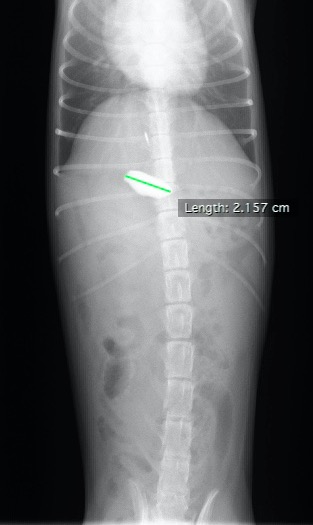

すぐにX線検査を行ったところ、胃内に石と思われる2㎝弱のX線不透過物が見つかりました。

横からのX線写真。白く写っているものが石と思われる異物です。参考のため、近くにあった石を一緒に写しています。